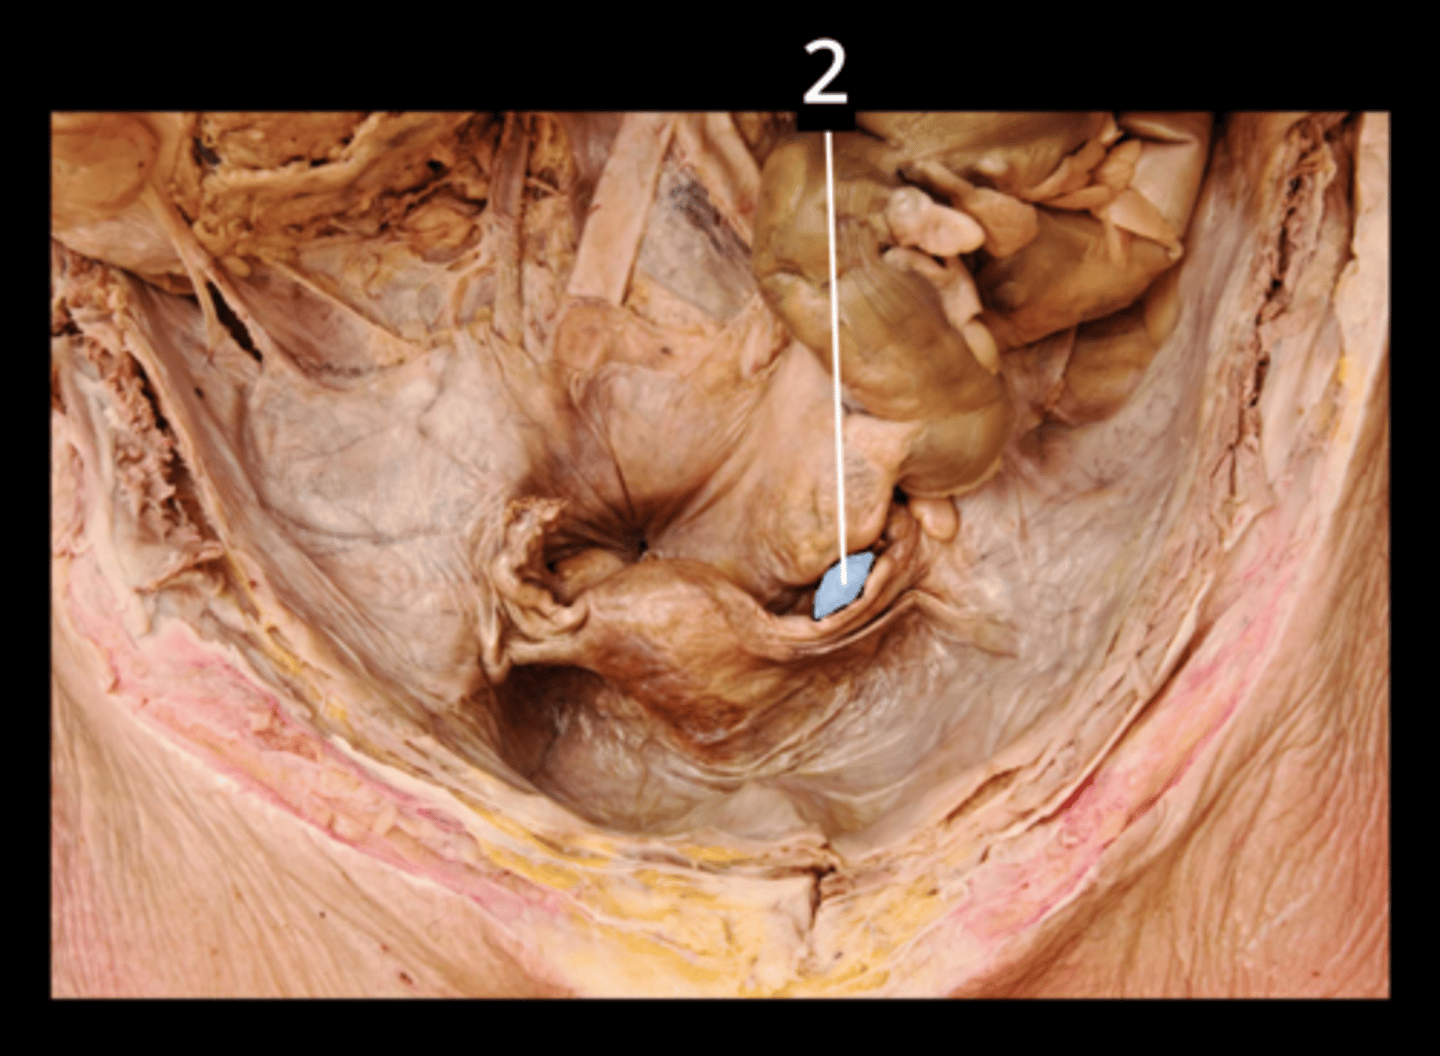

Ileocecal Valve